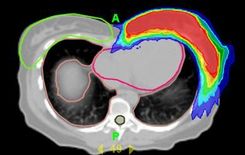

PET-CT geplante Strahlentherapie bei Lungenkrebs

Die PET/CT ist ein leistungsfähiges Hybridbildgebungsverfahren, das vor allem für die Diagnostik von Krebserkrankungen herangezogen wird. Es kombiniert die hochauflösende Positronen-Emissions-Tomographie PET mit der Computertomographie CT. Die PET kann Krebsgewebe anhand eines gesteigerten Stoffwechsels der erkrankten Zellen identifizieren. Die CT macht eine genaue Aufzeichnung des Körpers in 3D. Die Kombination beider Technologien ermöglicht eine eindeutige Lokalisierung des Tumors und eventueller Metastasen. Auf Basis dieser Daten lässt sich zum Beispiel eine Strahlenbehandlung bei Lungenkrebs präzise planen.